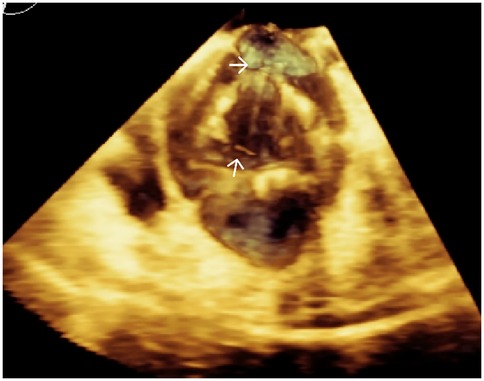

Transapical access was achieved via a small intercostal incision over the left ventricular apex, using a dedicated delivery catheter and J-valve system. Under fluoroscopic guidance and TEE monitoring, three U-shaped nitinol graspers were deployed into the aortic sinuses, demonstrating stable morphology and positioning. A 29 mm self-expanding valve was then deployed and securely seated within the graspers. Intraoperative TEE confirmed optimal prosthetic position and stability, with no paravalvular regurgitation; notably, two ACTs ruptured, neither compromising valve stability (Figure 2; Supplementary Video S4). The TAVR valve was subsequently decoupled from the delivery system. Following delivery system retrieval, aortic root angiography and TEE confirmed absence of AR, paravalvular leakage, or coronary obstruction, with stable stent position and normal prosthetic function (Figure 3; Supplementary Video S5).

Figure 3. Intraoperative TEE confirming stable prosthetic valve position, absence of paravalvular leakage, and normal leaflet function.